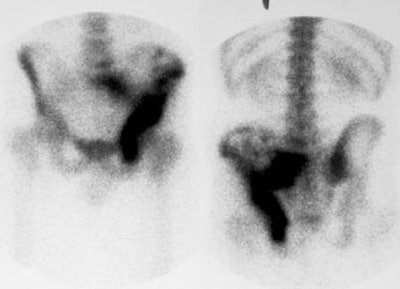

Ewings sarcoma of the pelvis: The bone scan demonstrates extensive, intense tracer uptake involving the left iliac wing, extending into the ischium and left sacrum. CT scan revealed a mixed, but predominantly sclerotic lesion involving the bone with an associated soft tissue mass. Note that the sacrum fails to demonstrate a CT abnormality. The T2 weighted images from the patients MR exam more clearly defines the lesion. Sacral involvement is clearly evident (white arrows) and there is also a large soft tissue component. |